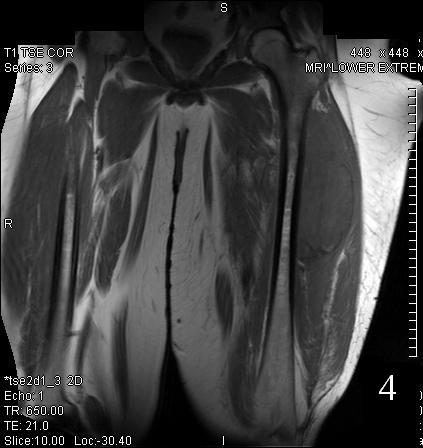

MRI

• Low to intermediate signal intensity on T1W

• High signal intensity on T2W

• Usually heterogeneous from necrosis and hemorrhage

Fig. 3

Fig. 4

Fig. 3-4 Axial (Fig. 3) and coronal (Fig. 4) T1 W MRI of the thigh shows an Extraskeletal Ewing Sarcoma that is iso-intense with the adjacent musculature.